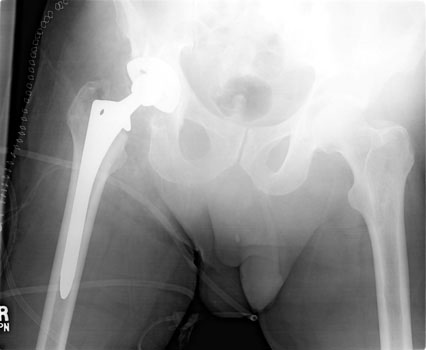

A B

Immediate post operative radiographs after left bipolar hemiarthroplasty (A)  and right total hip arthroplasty (B).